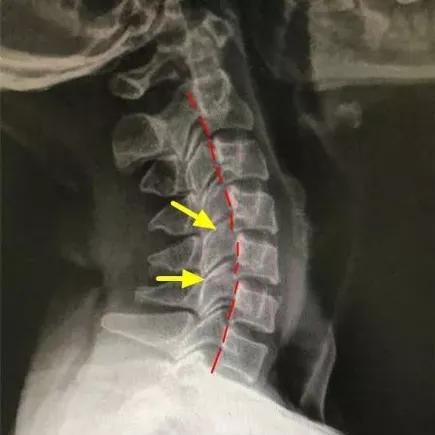

“颈椎有正常的生理弯曲,如果没有生理弯曲,甚至向相反的方向弯曲,称为反弓或反张。该患者本身患有颈椎病,属于颈椎不稳的情况,过山车项目快速的方向变动,更容易诱发颈椎疼痛。”接诊的广医三院中医科主任医师胥海斌解释说。在进行“骨、筋、脉”三联疗法综合治疗后,王女士颈椎疼痛得到缓解。

如果已经得了颈椎病,影像检查报告中,会有“动力性过伸位”“动力性过屈位”的检查项目,这两个项目是决定颈椎安全活动的关键,不同的颈椎病,需要不同的方式来进行康复训练。

如果“动力性过伸位”没有错位,但颈椎侧位片显示颈椎变直甚至出现“反弓”,那么就需要多抬头。